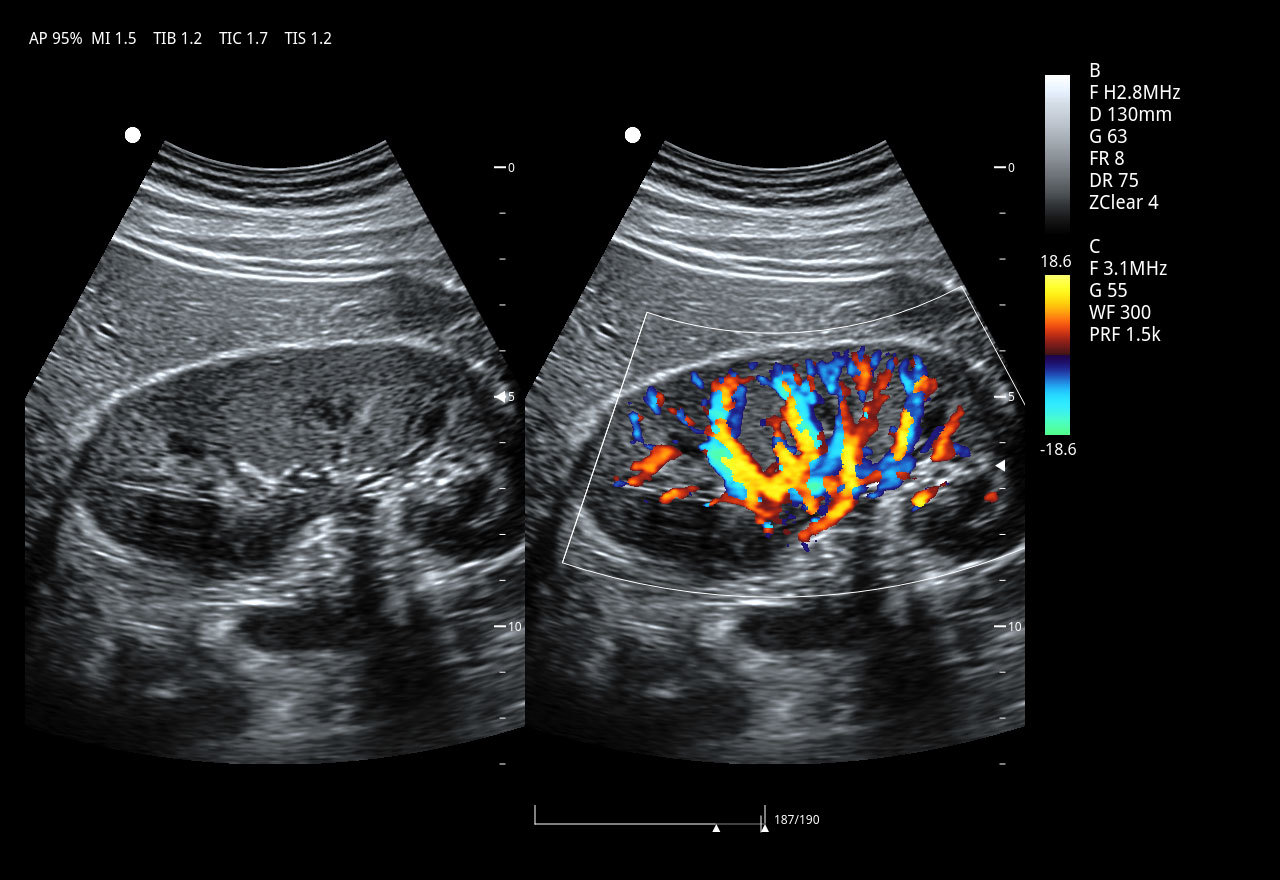

Imágenes clínicas extraordinarias

El Doppler Color ViV 20 es un ecógrafo de nueva generación diseñado para ofrecer una experiencia clínica superior con un equilibrio perfecto entre rendimiento, durabilidad y accesibilidad. Su arquitectura avanzada proporciona imágenes claras y precisas, permitiendo diagnósticos confiables en aplicaciones como abdomen, ginecología, vascular, partes blandas y más.

Práctico y fácil de usar, el ViV 20 integra funciones esenciales para el trabajo diario, con herramientas de medición completas, modos Doppler avanzados y optimización automática de imagen. Su diseño resistente garantiza una larga vida útil incluso en entornos de alta demanda, convirtiéndolo en una opción ideal tanto para clínicas pequeñas como para centros médicos con gran flujo de pacientes.